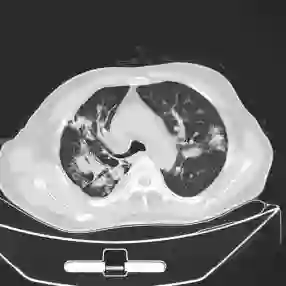

This paper proposes applying a novel deep-learning model, TBDLNet, to recognize CT images to classify multidrug-resistant and drug-sensitive tuberculosis automatically. The pre-trained ResNet50 is selected to extract features. Three randomized neural networks are used to alleviate the overfitting problem. The ensemble of three RNNs is applied to boost the robustness via majority voting. The proposed model is evaluated by five-fold cross-validation. Five indexes are selected in this paper, which are accuracy, sensitivity, precision, F1-score, and specificity. The TBDLNet achieves 0.9822 accuracy, 0.9815 specificity, 0.9823 precision, 0.9829 sensitivity, and 0.9826 F1-score, respectively. The TBDLNet is suitable for classifying multidrug-resistant tuberculosis and drug-sensitive tuberculosis. It can detect multidrug-resistant pulmonary tuberculosis as early as possible, which helps to adjust the treatment plan in time and improve the treatment effect.